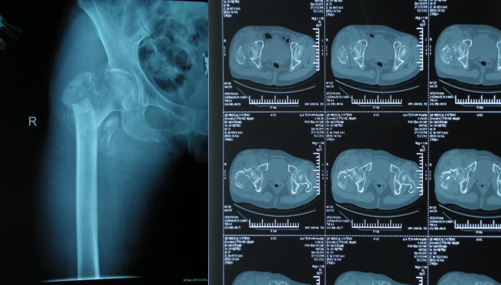

病理性骨折就是在某些疾病基础上出现的骨折。这其中发生率最高的原发疾病是结核、肿瘤和骨质疏松。它与单纯外伤性骨折不同,病理性骨折的骨头预先被某些病侵蚀、破坏、蛀空,再遇到轻微的外力,甚至没有外力只因自身的重力作用就可以自发骨折。大多数不需要CT、磁共振等高费用检查,只需拍X线片就可以大致判断出病变的性质、范围、破坏程度以及可能发生病理性骨折的危险性。

股骨转子间病理性骨折是现代老年患者常见的病理性骨折,多数有肿瘤类疾病病史。现代医学手术为治疗首选,应用特制肿瘤假体,可以很好的解决因骨质被破坏而引起的骨质缺损及关节周围重建等问题,早期离床下地活动,减少长期卧床的并发症发生,延长有效寿命,提高生活质量。

患者中老年女性,67岁,入院前在家中仅为拾取东西,在下蹲过程中即听到右髋部有响声,随即倒地。当时患者无任何外力影响,因伤后右髋部疼痛,关节活动受限,而到我院就诊,门诊收入院治疗。

X线及CT提示右股骨转子间骨质破坏,可明确诊断为右股骨转子间病理性骨折。我科行手术治疗,给予肿瘤假体置换,并行关节周围重建,手过程非常顺利。

术后仅2周左右,右髋关节床上活动基本达到正常,3周时逐渐下地,在助行器及家人协助下行走,未感到明显不适。1个月基本完全康复,生活达到自理,患者及家属对于治疗效果感到非常满意。